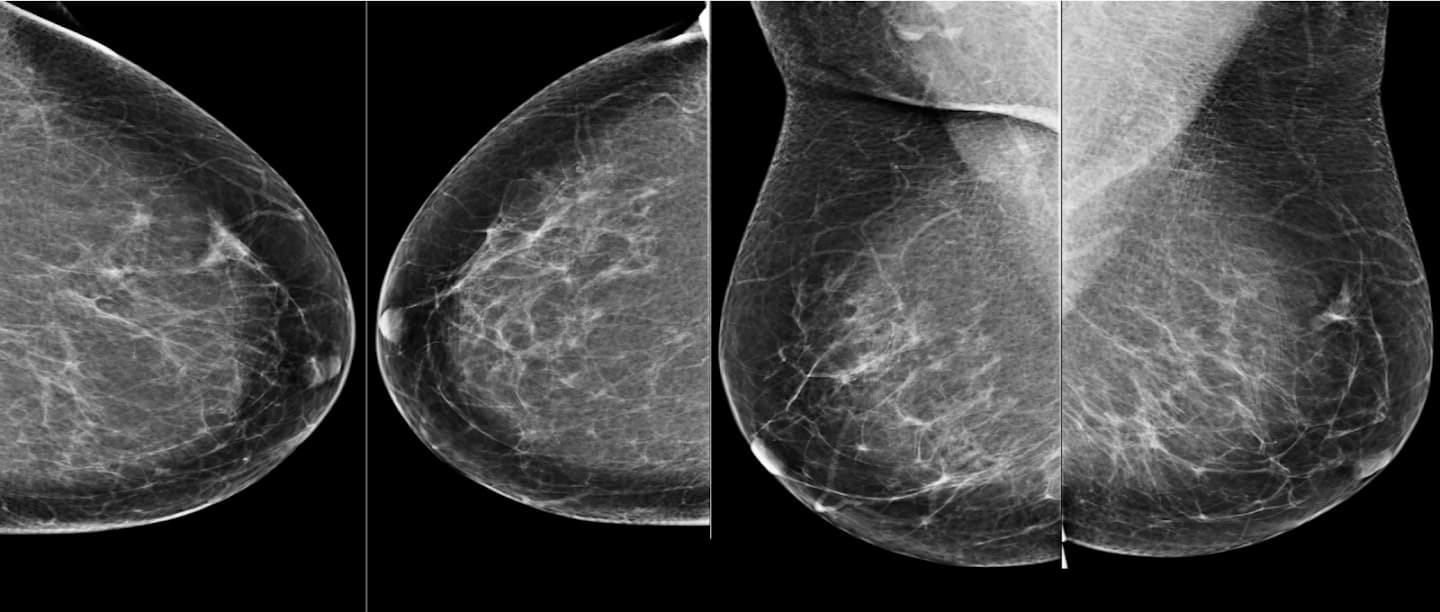

最も複雑な機械学習には、深層学習(ディープラーニング)や、結果を予測する特徴や変数を何段階も持つニューラルネットワークモデルがあるが、医療分野における深層学習の一般的な応用例としては、放射線画像中の癌の可能性がある病変(病気の過程であらわれる生体の局所変化)の認識が挙げられる。深層学習は、ラジオミクス(人間の目で認識できる範囲を超えて、画像データ中の臨床的に関連する特徴を検出すること)への応用が増えている。ラジオミクスと深層学習は、いずれも腫瘍に特化した画像解析で最もよく見られるものだ。これらを組み合わせることで、CAD(Computer-Aided Detection)と呼ばれる前世代の画像解析自動化ツールよりも高い精度の診断が可能になると考えられる。

このような技術のほとんどは臨床現場ではなく、研究所やテクノロジー企業に存在している。例えば、Google傘下のAI研究所であるDeepMindは、乳がん診断を行うAIモデルを開発しており、2020年1月に「Nature」に論文として発表された研究によると、乳房X線撮影像(マンモグラム)を使った乳がん診断で「AIの方が人間の専門医より偽陽性、偽陰性の判定が少なく、正確な結果を出した」と主張している。研究によると、チームは米国と英国の臨床現場を代表する2つの大規模データセットを用いて、偽陽性(陰性であるにも関わらず陽性結果となること)を5.7%/1.2%(米国/英国)、偽陰性を9.4%/2.7%(米国/英国)、減少させることができた。